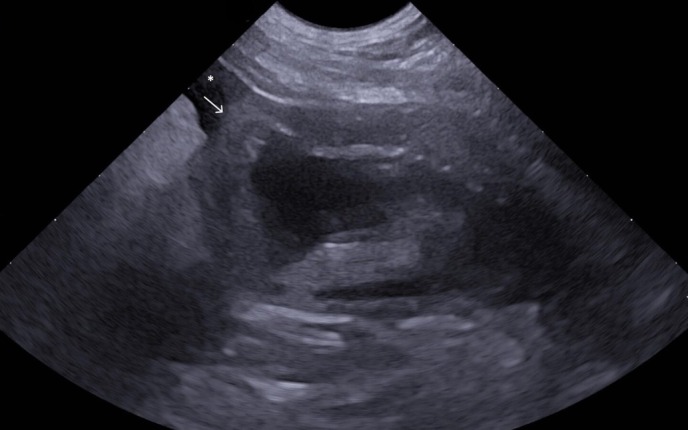

一只10岁雄性杂交犬出现呕吐和无尿。这只狗住在室内,主人没有报告任何创伤。超声检查和逆行尿道造影显示存在膀胱渗漏。行剖腹手术修复膀胱撕裂,同时行膀胱壁活检。组织病理特征为淋巴浆细胞性膀胱炎伴出血和肌层内多灶性纤维化区。自发性膀胱破裂无外伤证据是一个众所周知的,虽然罕见,条件在人类医学。在本病例中发现的慢性炎症,以及纤维化,导致膀胱壁变弱,导致穿孔。这是第一例有文献记载的继发于慢性炎症的自发性膀胱破裂的兽医病例,强调了将这种情况包括在无潜在创伤的尿腹膜患者的鉴别诊断中的重要性。

A 10-year-old male mixed-breed dog presented with vomiting and anuria. The dog was living indoors, and no trauma was reported by the owner. Ultrasonography and a retrograde urethrogram revealed the presence of a urinary bladder leakage. A celiotomy was performed to repair a urinary bladder tear, along with a biopsy of the urinary bladder wall. Histopathological features consisted of lymphoplasmacytic cystitis with haemorrhages and multifocal fibrotic areas within the muscular layers. Spontaneous rupture of the urinary bladder without evidence of trauma is a well-known, though rare, condition in human medicine. The chronic inflammation detected in the present case, along with fibrosis, caused the weakening of the urinary bladder wall, leading to perforation. This is the first documented veterinary case of spontaneous rupture of the urinary bladder secondary to chronic inflammation and highlights the importance of including this condition in the differential diagnosis of patients presenting with uroperitoneum without underlying trauma.